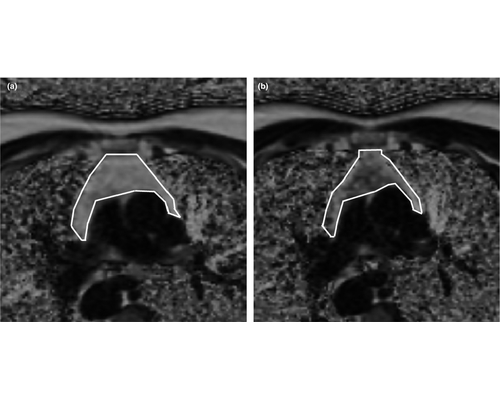

华中科技大学谢庆国教授团队发明的全数字PET/CT,已于2019年5月31日通过国家药品监督管理局注册审批,获得市场准入和对外销售资质。这意味着国产全数字PET打破国际技术垄断,我国高端医疗仪器开发取得重大突破。

PET是正电子发射断层成像的简称,是继超声、CT和核磁共振之后当今的尖端医学影像技术,在恶性肿瘤、神经系统疾病、心血管疾病等重大疾病早期诊断、疗效评估、病理研究等方面,具有极大应用价值。